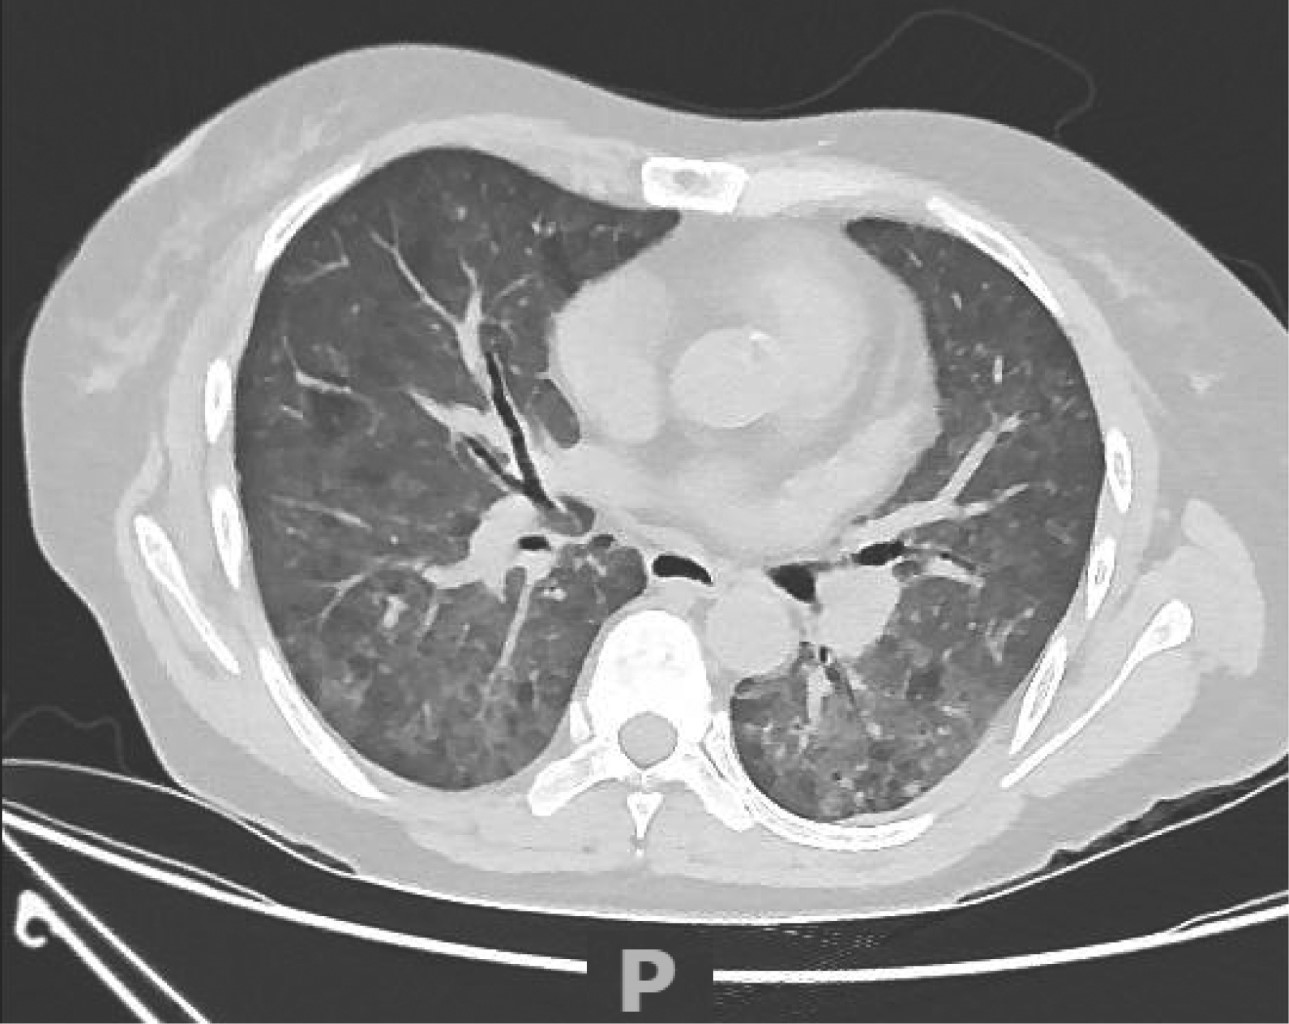

Figure 2